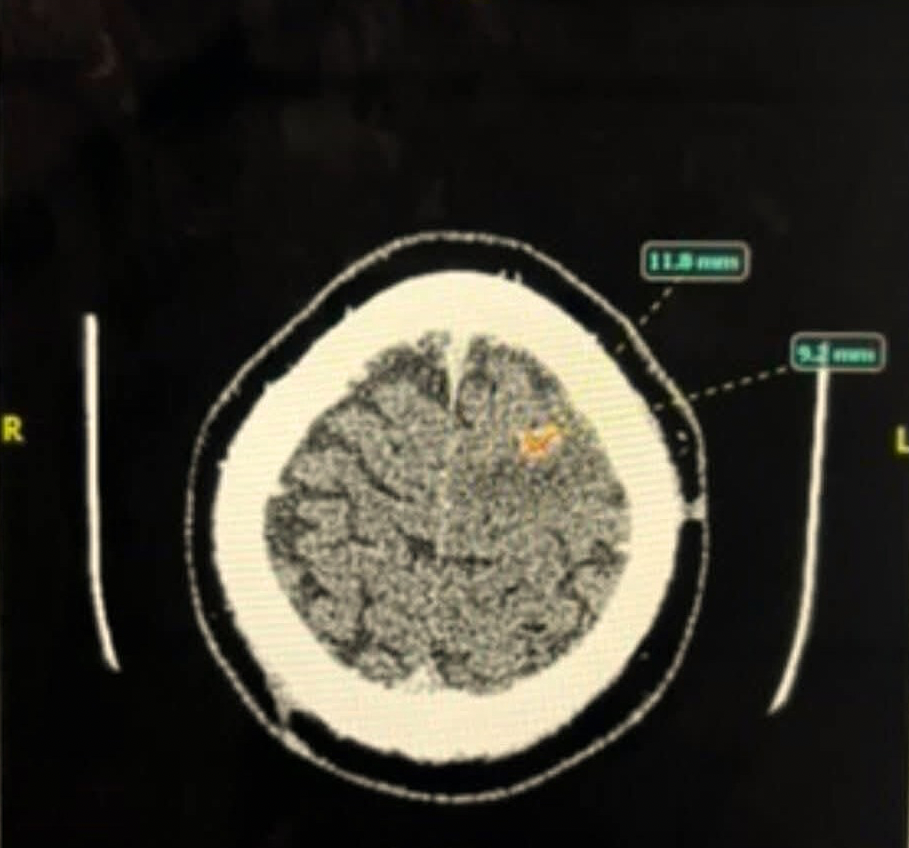

’n Skandering van die gewas wat in Augustus 2024 in Vincent se brein waargeneem is. Foto verskaf

Dit was helaas nie die einde van sy mediese uitdagings nie. ’n Gewas van 12 mm is in sy brein ontdek ná ’n epileptiese toeval op 4 Augustus. Hy het ná die bestraling beter begin voel, maar sy ledemate het stelselmatig weer lam geraak.

Die grootste gewas het 4 cm groot geword, en verskeie kleiner gewasse (3 tot 5 mm) het gevorm. Een van hierdie gewasse was in die middel van sy brein, waar dit nie geopereer kon word nie.